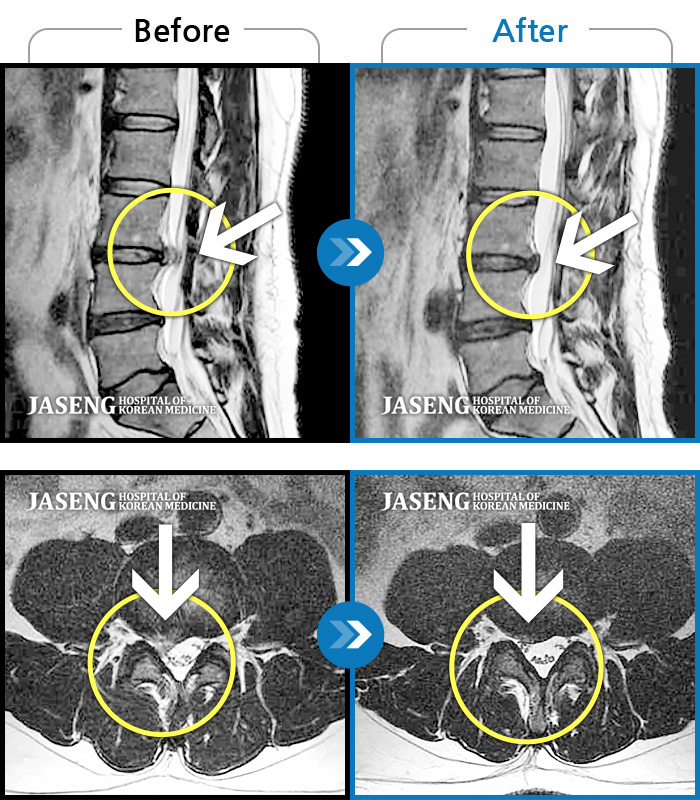

허리디스크

잠실 · 한상욱 원장

허리, 우측 엉치와 다리 후면 및 발끝까지 저림과 통증이 심하고 힘까지 빠진다.

촬영시기

2022.06.15 ~ 2022.11.11

2022.12.02